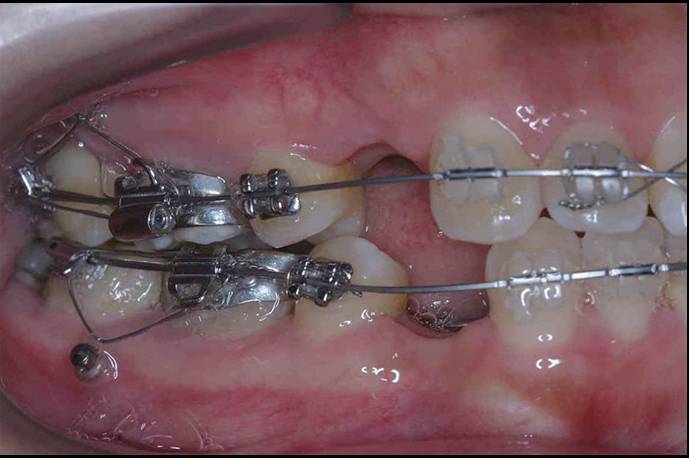

支抗的种类有哪些 正畸矫治过程中,任何施于矫治牙使其移动的力必然同时产生一个方向相反、大小相同的力,而支持这种移动矫正牙体引起的反作用力的情况称为“支抗”。... 牙齿矫正 阙德厚 1328 2023-12-18

正畸中牙齿移动的机制分析与矫治器设计 矫治器是正畸过程中用来移动牙齿的装置,所以谈到矫治器的设计和应用,有必要先分析一下正畸过程中牙齿的移动方式是怎样的,如何才能产生这些预期的牙齿移动。... 牙齿矫正 范姜英杰 770 2023-12-12